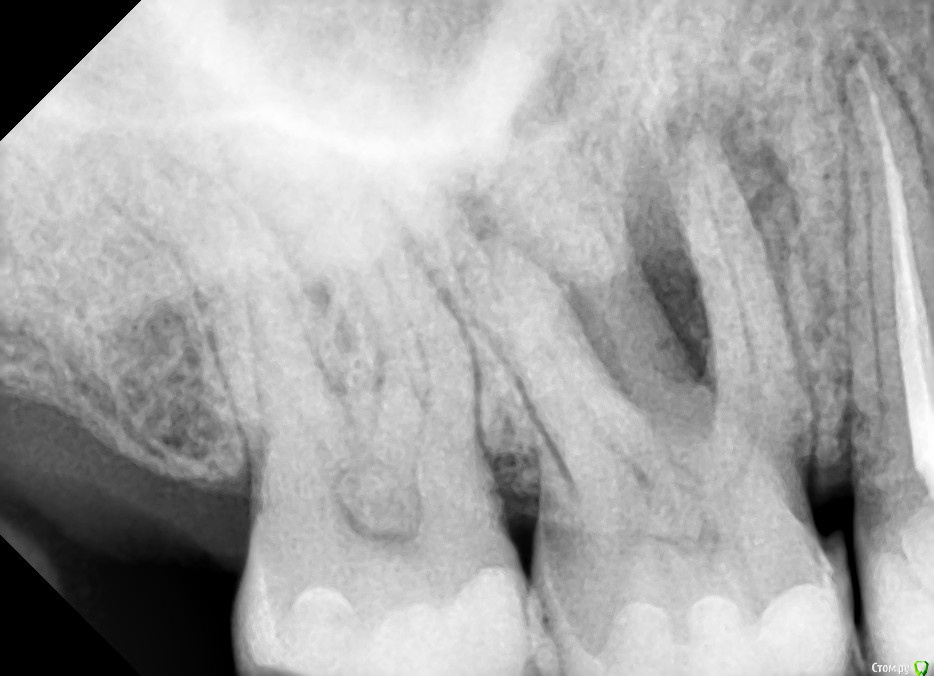

Елизавета С Опубликовано 19 декабря, 2018 Поделиться Опубликовано 19 декабря, 2018 (изменено) Подскажите,пожалуйста,дорогие специалисты,ваше мнение.. Вехний зуб,6, со свищем гноем, каналы не пломбированы в этом зубе. Часть специалистов однозначно за удаление говорят,потому что верхние зубы почему-то не поддаются терапии и гайморова мазуха в нее может попасть гной из десны..и это опасно и бесполезно проводить лечение и начнется гайморит, и все равно потом удалять.А другая часть говорит,что вполне можно пробовать лечить и с успехом 50 на 50... Совершенно запуталась..нужно стороннее мнение спасибо! Изменено 19 декабря, 2018 пользователем Елизавета С 1 Ссылка на комментарий

Neilrus Опубликовано 20 декабря, 2018 Поделиться Опубликовано 20 декабря, 2018 смирнова 16.jpg Подскажите,пожалуйста,дорогие специалисты,ваше мнение.. Вехний зуб,6, со свищем гноем, каналы не пломбированы в этом зубе. Часть специалистов однозначно за удаление говорят,потому что верхние зубы почему-то не поддаются терапии и гайморова мазуха в нее может попасть гной из десны..и это опасно и бесполезно проводить лечение и начнется гайморит, и все равно потом удалять.А другая часть говорит,что вполне можно пробовать лечить и с успехом 50 на 50... Совершенно запуталась..нужно стороннее мнение спасибо!я за лечение если готовы к финансовыми рисками (в случае неудачи - удаление) Ссылка на комментарий